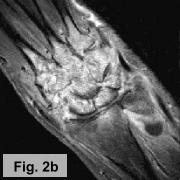

IMAGING FINDINGS:  A triple-phase bone scan was obtained on AIC's dual-head nuclear camera.  Fig. 1a-c show the angiographic (flow) images, blood pool images, and delayed (static) images of the wrists, respectively.  They demonstrate marked increased uptake in the left wrist in all 3 phases of the study.  Fig. 2a-b are selective pre and post-contrast MRI images of the left wrist showing precontrast T1-weighted (Fig. 1a) and postcontrast T1-weighted with Fat SAT (Fig. 1b).  They demonstrate diffuse edema in the marrow of all the carpal bones and proximal metacarpal bones with diffuse enhancement of the marrow and surrounding synovium.  X-rays (not shown) revealed diffuse osteopenia and erosions of the carpal bones.

DIFFERENTIAL DIAGNOSIS:  The bone scan findings are usually seen with osteomyelitis, but diffuse carpal involvement is unusual.  Increased uptake on all 3 phases can also be seen with Reflex Sympathetic Dystrophy (RSD) or an inflammatory process.  The MRI and x-ray findings are more compatible with an inflammatory process, particularly rheumatoid arthritis, with diffuse synovitis and erosions and reactive marrow changes, although this is a late presentation for the patient's age.